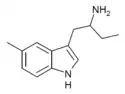

List of substituted α-alkyltryptamines

α-Alkyltryptamines are a group of substituted tryptamines which possess an alkyl group, such as a methyl or ethyl group, attached at the alpha carbon, and in most cases no substitution on the amine nitrogen.[17][18][19] α-Alkylation of tryptamine makes it much more metabolically stable and resistant to degradation by monoamine oxidase, resulting in increased potency and greatly lengthened half-life.[19] This is analogous to α-methylation of phenethylamine into amphetamine.[19]

Many α-alkyltryptamines are drugs, acting as monoamine releasing agents, non-selective serotonin receptor agonists, and/or monoamine oxidase inhibitors,[20][21][22][23] and produce psychostimulant, entactogen, and/or psychedelic effects.[17][18][19] The most well-known of these agents are α-methyltryptamine (αMT) and α-ethyltryptamine (αET), both of which were used clinically as antidepressants for a brief period of time in the past and are abused as recreational drugs.[18][19] In accordance with its action as a dual releasing agent of serotonin and dopamine, αET has been found to produce serotonergic neurotoxicity similarly to amphetamines like MDMA and PCA, and the same is also likely to hold true for other serotonin and dopamine-releasing α-alkyltryptamines such as αMT, 5-MeO-αMT, and various others.[24]

4-Methyl-αMT | 1-methyl-2-(4-methyl-1H-indol-3-yl)-ethylamine | 3569-29-7 |

4-Methyl-αET | 1-(4-Methyl-1H-indol-3-yl)butan-2-amine | 28289-30-7 |

5-Methyl-αET | 1-(5-methyl-1H-indol-3-yl)butan-2-amine | 1380148-21-9 |